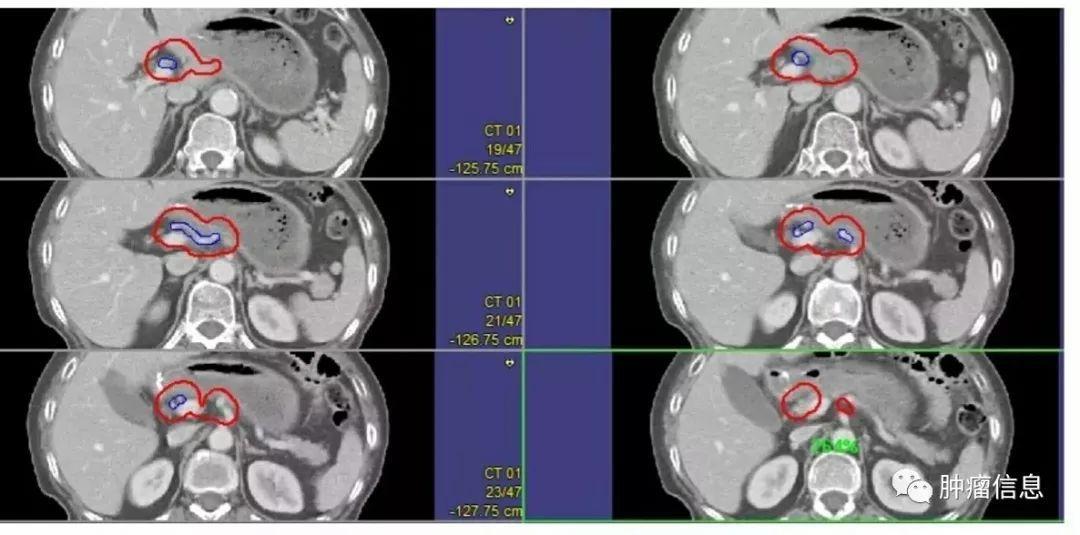

髂总淋巴结

从腹主动脉分叉到髂内动脉的分支之间的髂总血管周围淋巴结。上界:主动脉分叉或腰4-5间隙下界:髂总动脉分叉前界:动静脉前7mm后界:L5椎体和骶岬(包括腰大肌与椎体旁间隙)外侧界:动静脉旁7mm(腰大肌)勾画时应包括血管及周围7mm区域,(包括骨、肌肉、小肠),以及所有可疑淋巴结、淋巴囊肿、手术银夹。

髂内淋巴结

髂内动静脉周围淋巴结上界:髂总分叉下界:尾骨肌上缘或坐骨棘其他边界具体范围见下图所示:

髂外淋巴结

上界:髂总分叉下界:股骨头上缘其他边界见下图:

骶前淋巴结

图中蓝色区域上界:髂总分叉下界:S2下缘或梨状肌上缘其他边界见下图:

闭孔淋巴结

上界:骶髂关节的下界(连接髂内区)下界:闭孔上部分(股骨颈上缘)其他边界见下图: